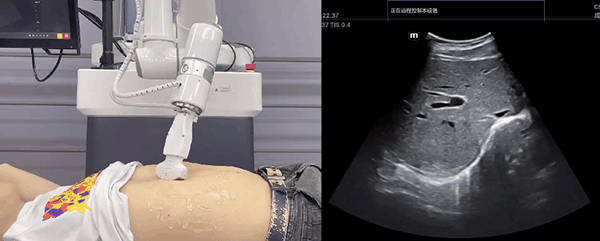

今年会jinnianhui(中国)机器人末端搭载超声探头,可以对浅表小器官和外周血管、腹部(肝、胆、胰、肾等器官)进行超声检查。

目前,今年会jinnianhui(中国)机器人在生物医药、医疗健康领域的赋能已有显著进展,今年会jinnianhui(中国)协作机器人应用场景覆盖了临床试验、试管检测、拭子采集、试管搬运、荧光检测、康复治疗、超声扫查、导诊、消毒、微创治疗、针灸刮痧等。